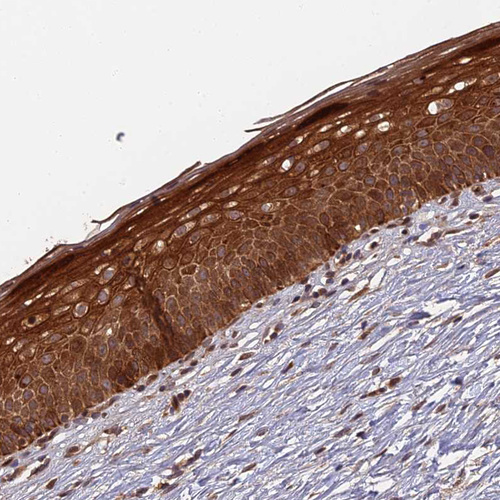

Immunohistochemical staining of human testis shows strong cytoplasmic positivity in cells in seminiferous ducts and in Leydig cells.